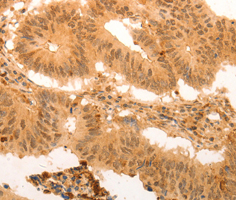

Immunohistochemistry of paraffin-embedded human prostate using SUMO3 antibody.